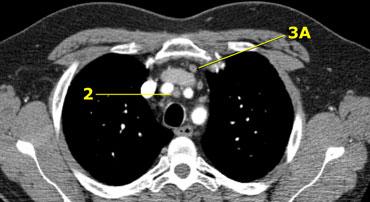

3. Hạch trước mạch máu và trước cột sống

Hạch nhóm 3 không nằm kề khí quản như hạch nhóm 2.

Chúng có thể là:

3A nằm phía trước các mạch máu, hoặc

3B nằm phía sau thực quản, vốn nằm ở vị trí trước cột sống.

Hạch nhóm 3 không thể tiếp cận bằng nội soi trung thất.

Bên trái là hạch 3A nằm trong khoang trước mạch máu.

Lưu ý cũng có các hạch cạnh khí quản dưới bên phải, tức là hạch nhóm 4R.